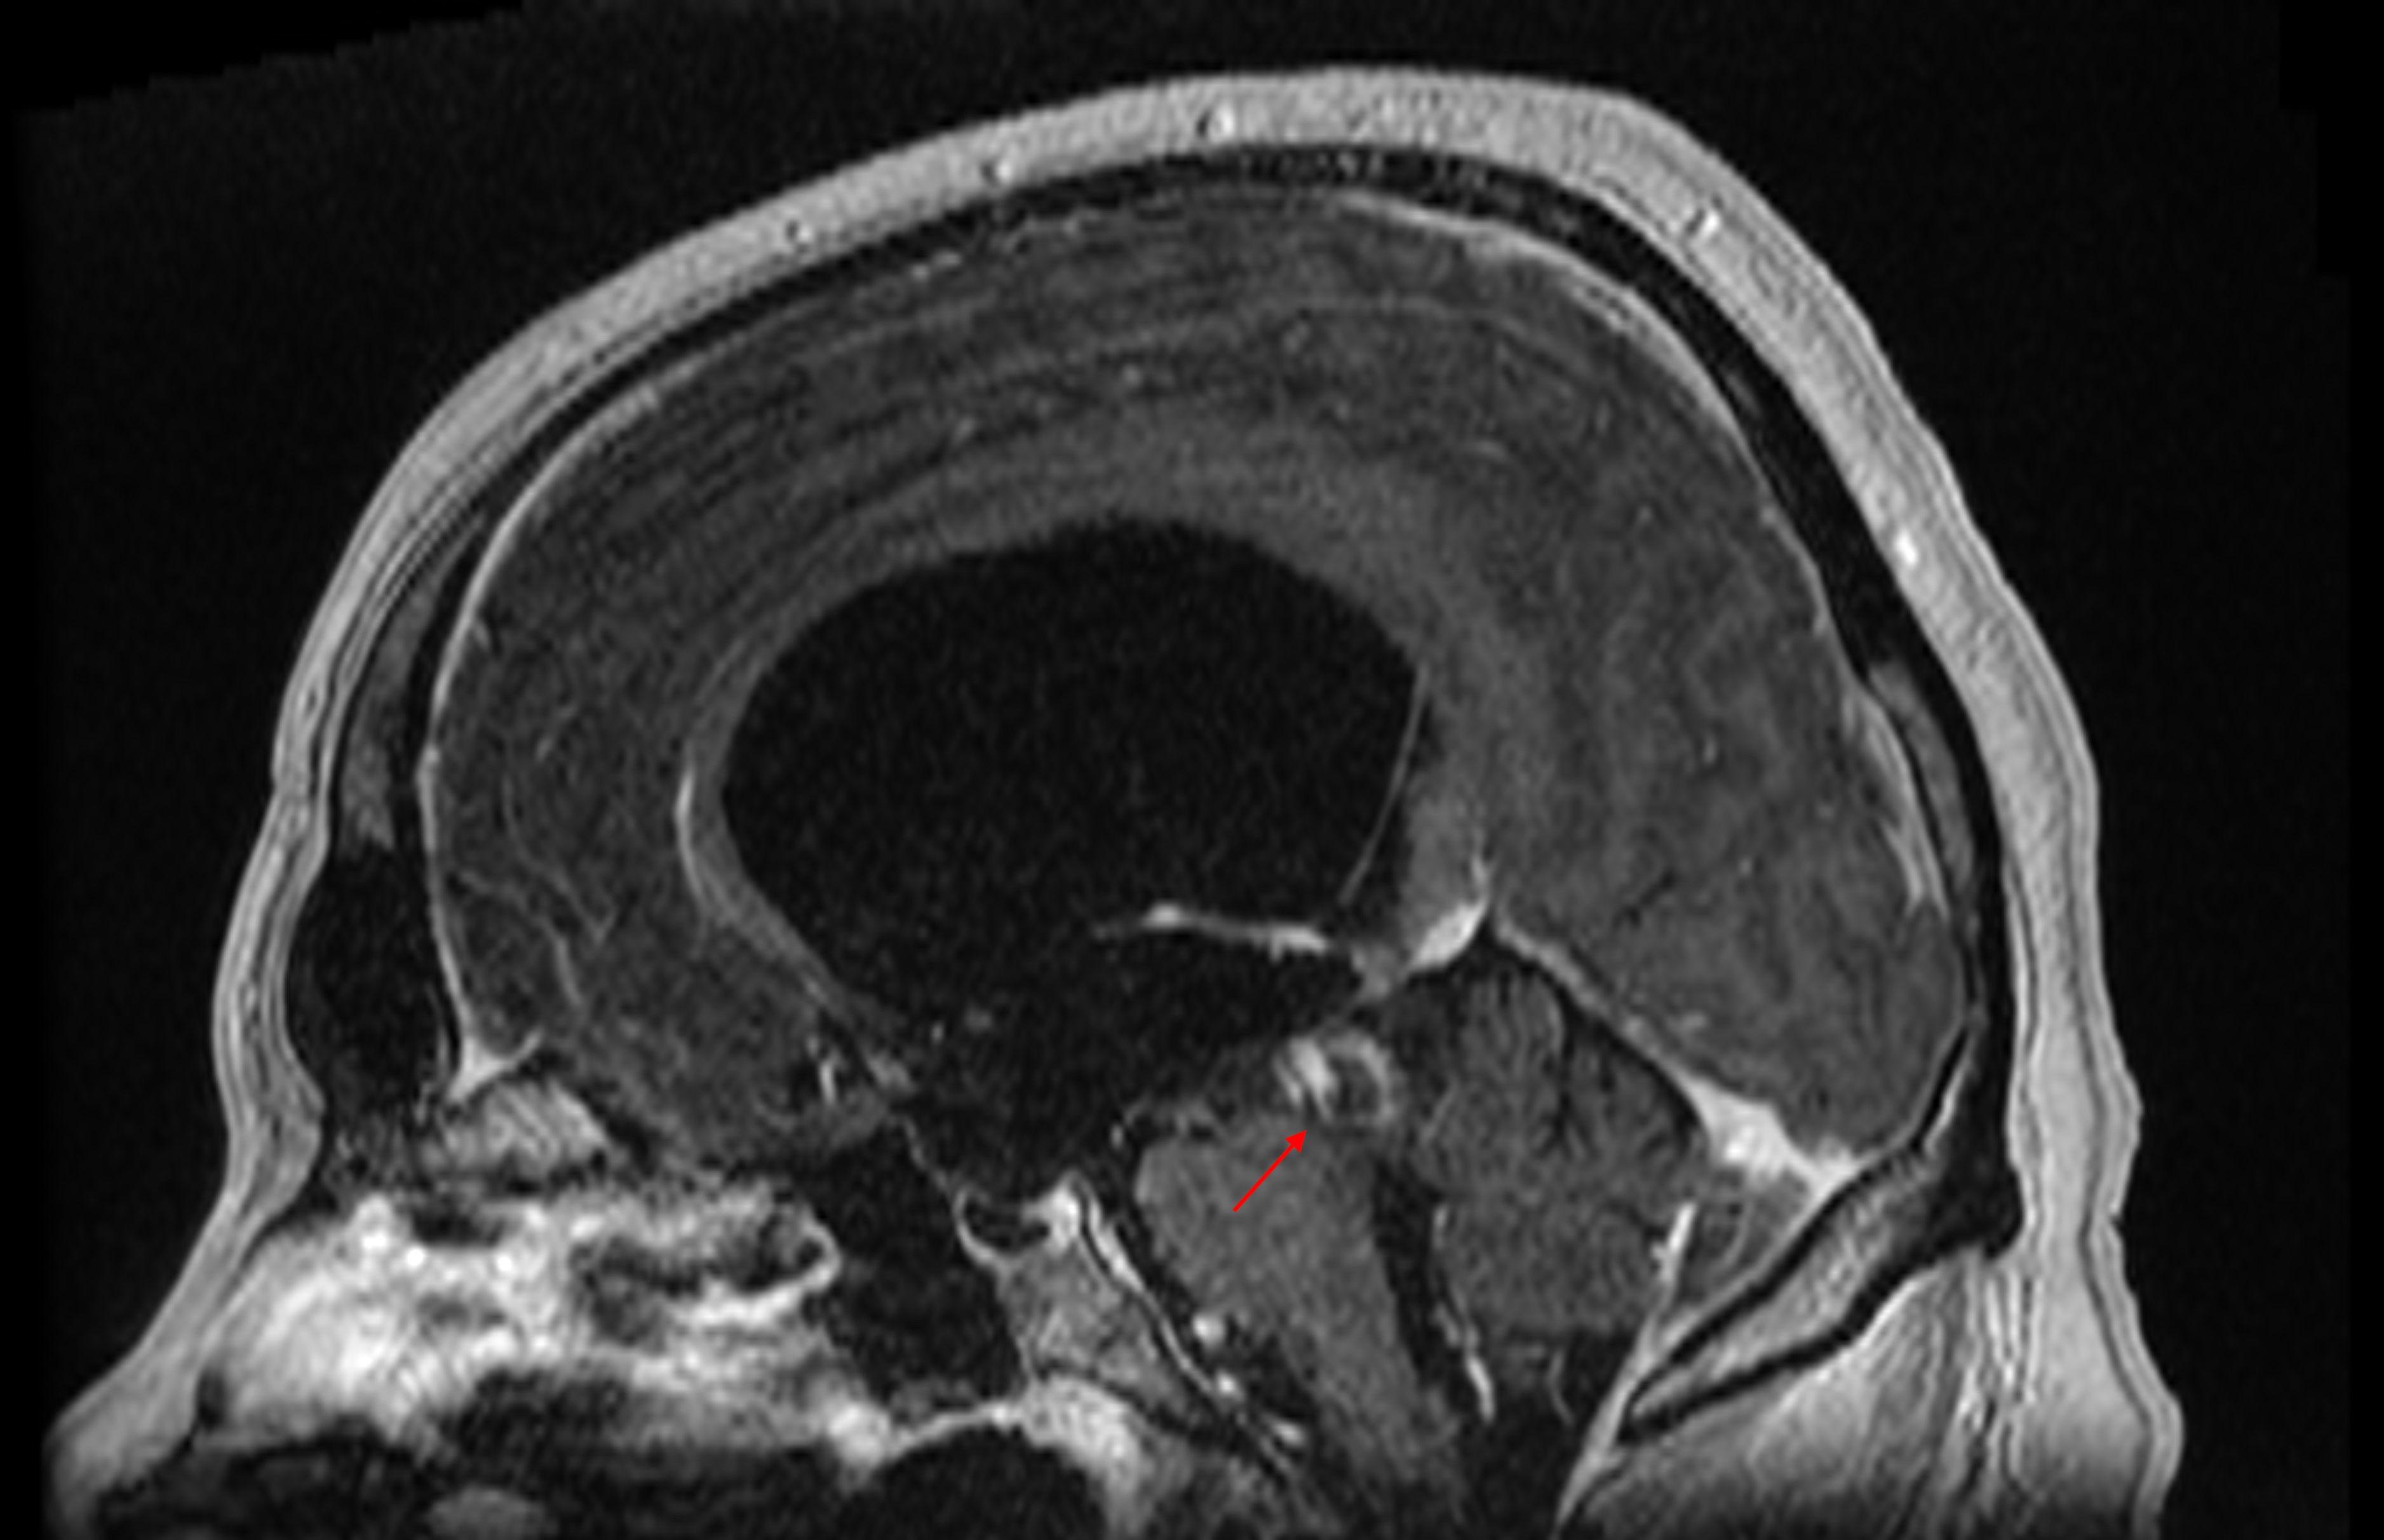

Pathologies of the pineal gland region are frequently encountered in daily neurosurgical practice. It is important to remember that, besides usually asymptomatic pineal gland cysts, neoplasms of a different origin may also occur in this region. The rarity of the most dangerous lesions – pineal gland apoplexy and pineal tumors – might cause problems with proper diagnosis and treatment. Their occurrence is commonly associated with symptomatic hydrocephalus caused by aqueductal stenosis. Currently, in such cases, endoscopic procedures, including endoscopic third ventriculostomy (ETV), are commonly and widely chosen as treatment options. Endoscopic procedures not only enable decompression of hydrocephalus but also further diagnosis of its cause. Herein, we present 3 case reports of endoscopic treatment with ETV performed in patients with hydrocephalus related to pineal region pathologies.